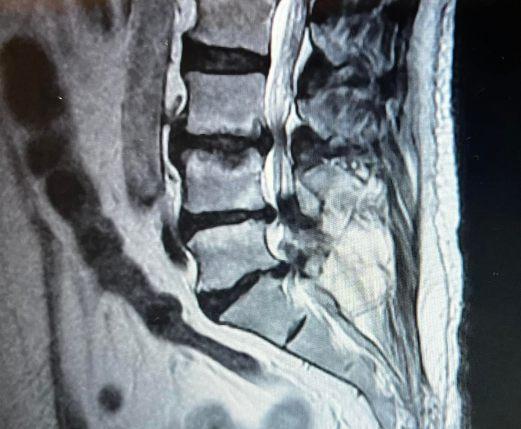

Cirujano ortopedista y traumatólogo, especializado en cirugía de columna.

Cirugía de columna

Cirugía de columna pediátrica

Trauma de urgencia

Trauma extrahospitalaria

Cirugía mínima invasiva

Hernias discales

Escoliosis

Dolores ciáticos, lumbares y cervicales

Salud vertebral para una vida plena